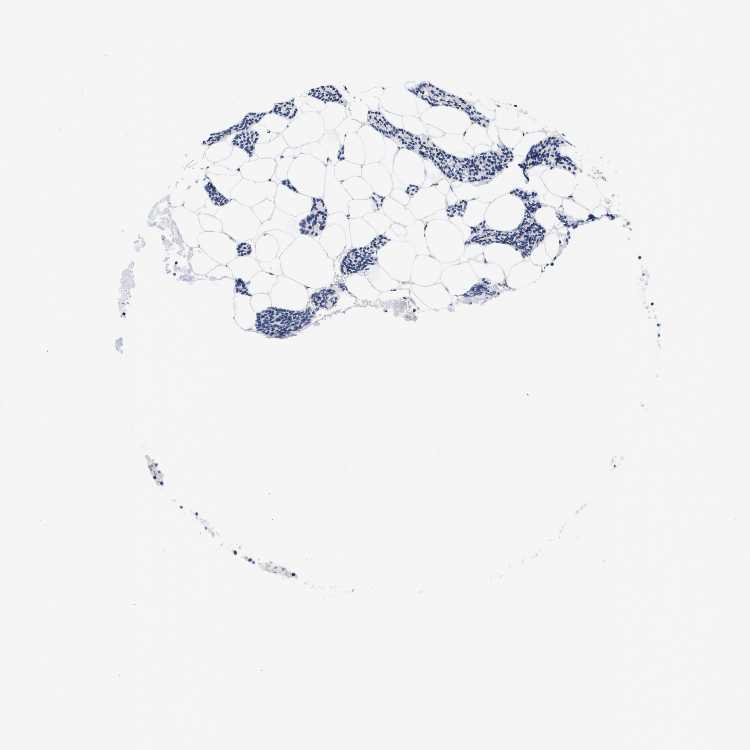

TISSUE PRIMARY DATA PARATHYROID GLAND Show tissue menu

PARATHYROID GLAND - Antibody stainingi

Antibody staining in the annotated cell types in the current human tissue is reported as not detected, low, medium, or high, based on conventional immunohistochemistry profiling in selected tissues. This score is based on the combination of the staining intensity and fraction of stained cells.

Each image is clickable and will lead to virtual microscopy that enables deeper exploration of all samples and also displays staining intensity scores, fraction scores and subcellular localization as well as patient and tissue information for each sample.

Antibody HPA000635Antibody CAB017444

Glandular cells LowNot detected